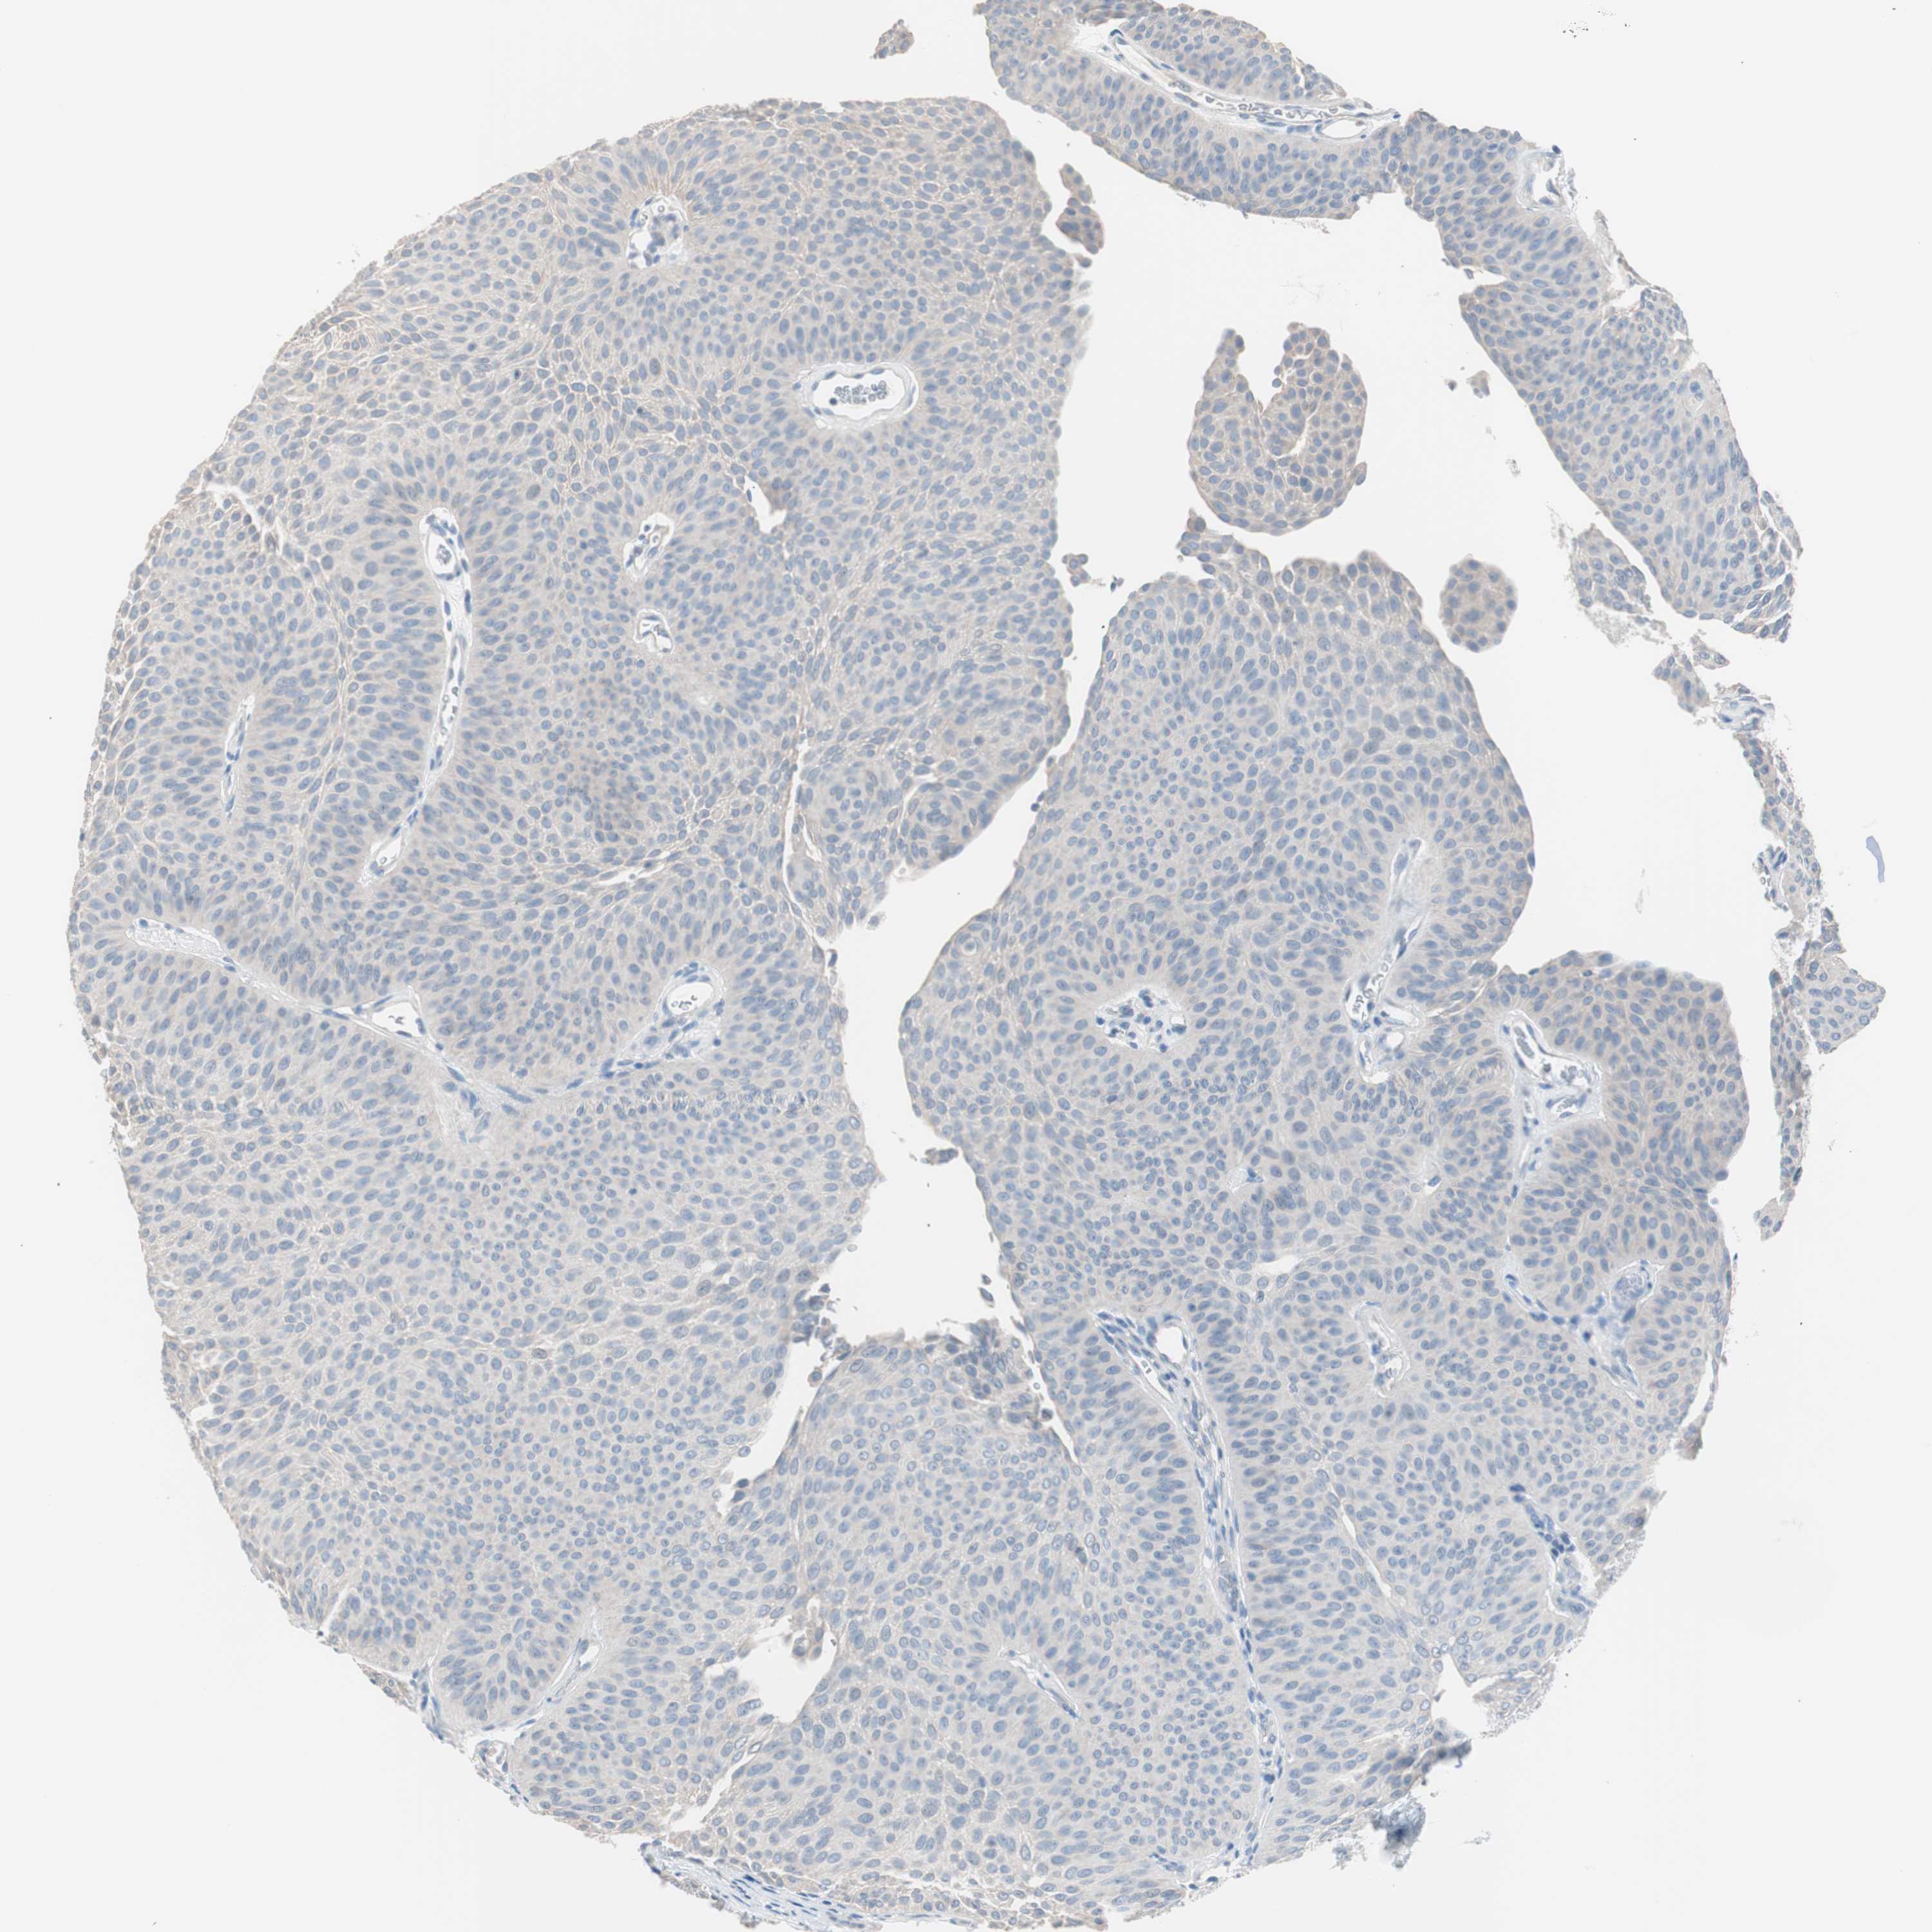

UROTHELIAL CANCER - Protein expressioni

A mouse-over function shows sample information and annotation data. Click on an image to view it in a full screen mode. Samples can be filtered based on level of antibody staining by selecting one or several of the following categories: high, medium, low and not detected. The assay and annotation is described here.

Note that samples used for immunohistochemistry by the Human Protein Atlas do not correspond to samples in the TCGA dataset.

Antibody stainingi

Antibody staining in the annotated cell types in the current human tissue is reported as not detected, low, medium, or high, based on conventional immunohistochemistry profiling in selected tissues. This score is based on the combination of the staining intensity and fraction of stained cells.

Each image is clickable and will lead to virtual microscopy that enables deeper exploration of all samples and also displays staining intensity scores, fraction scores and subcellular localization as well as patient and tissue information for each sample.

Antibody HPA006884

Antibody HPA006885

Antibody CAB002452

Urothelial carcinoma, Low grade

Urothelial carcinoma, High grade

Adenocarcinoma, NOS